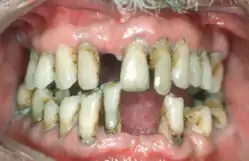

Periodontal disease, also known as gum disease, is a set of inflammatory conditions affecting the tissues surrounding the teeth.[5] In its early stage, called gingivitis, the gums become swollen and red and may bleed.[5] It is considered the main cause of tooth loss for adults worldwide.[7][8] In its more serious form, called periodontitis, the gums can pull away from the tooth, bone can be lost, and the teeth may loosen or fall out.[5] Bad breath may also occur.[1]

![]() | |

| Radiograph showing bone loss between the two roots of a tooth (black region). The spongy bone has receded due to infection under tooth, reducing the bony support for the tooth. | |